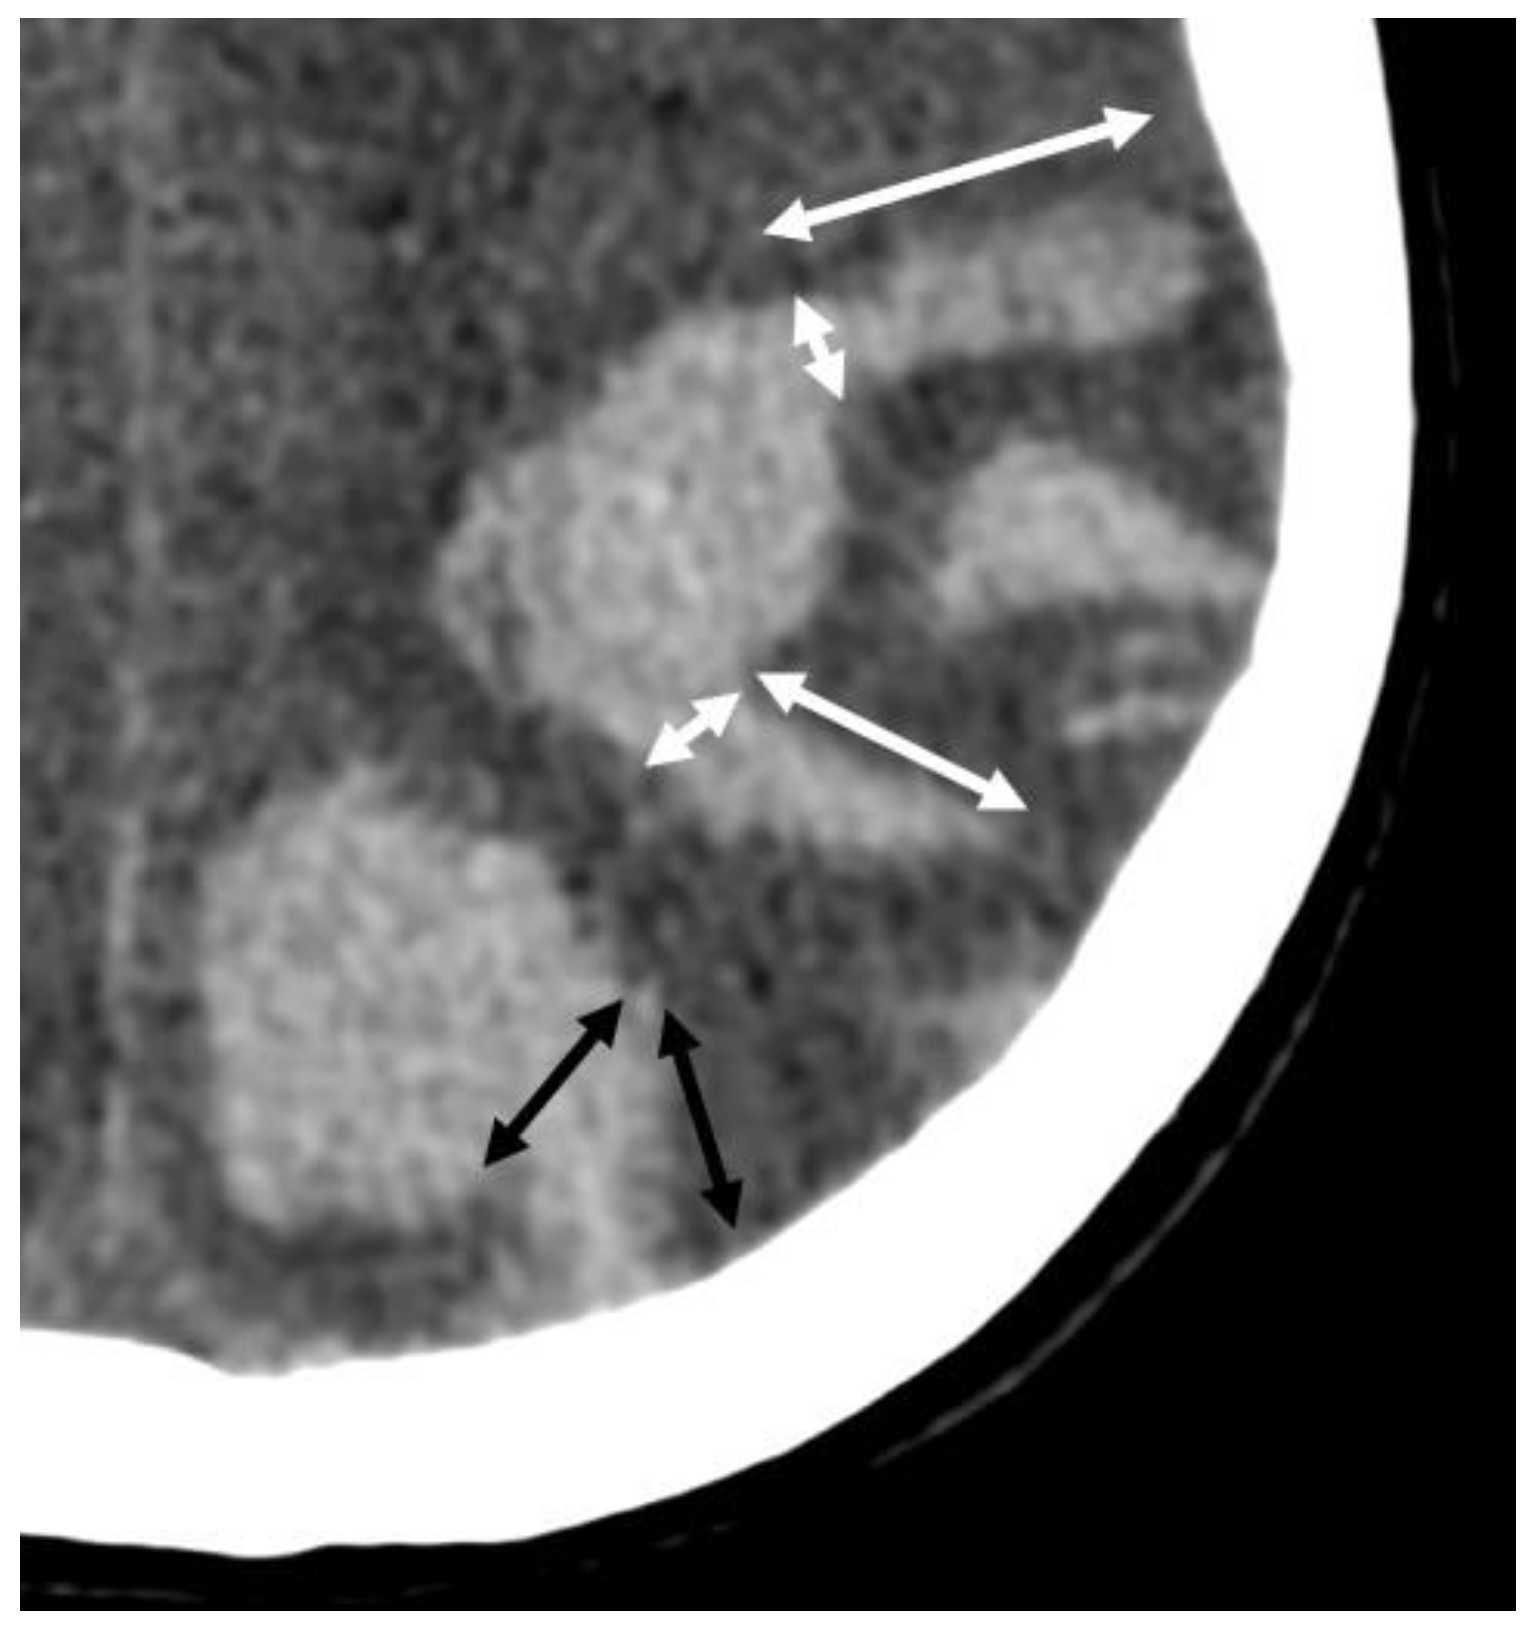

5.1.1. Lobar Hemorrhages

- Baron, J.-C.; Boulouis, G.; Benzakoun, J.; Schwall, C.; Oppenheim, C.; Turc, G.; Varlet, P. Cerebral amyloid angiopathy-related acute lobar intra-cerebral hemorrhage: Diagnostic value of plain CT. J. Neurol. 2022, 269, 2126–2132. [Google Scholar] [CrossRef]

- Rodrigues, M.A.; Samarasekera, N.; Lerpiniere, C.; Humphreys, C.; McCarron, M.O.; White, P.M.; Nicoll, J.A.R.; Sudlow, C.L.M.; Cordonnier, C.; Wardlaw, J.M.; et al. The Edinburgh CT and genetic diagnostic criteria for lobar intracerebral haemorrhage associated with cerebral amyloid angiopathy: Model development and diagnostic test accuracy study. Lancet Neurol. 2018, 17, 232–240. [Google Scholar] [CrossRef]

- Baron, J.-C.; Jensen-Kondering, U.; Sacco, S.; Posener, S.; Benzakoun, J.; Pallud, J.; Oppenheim, C.; Varlet, P.; Turc, G. Can novel CT-and MR-based neuroimaging biomarkers further improve the etiological diagnosis of lobar intra-cerebral hemorrhage? J. Neurol. 2023, 270, 582–588. [Google Scholar] [CrossRef]